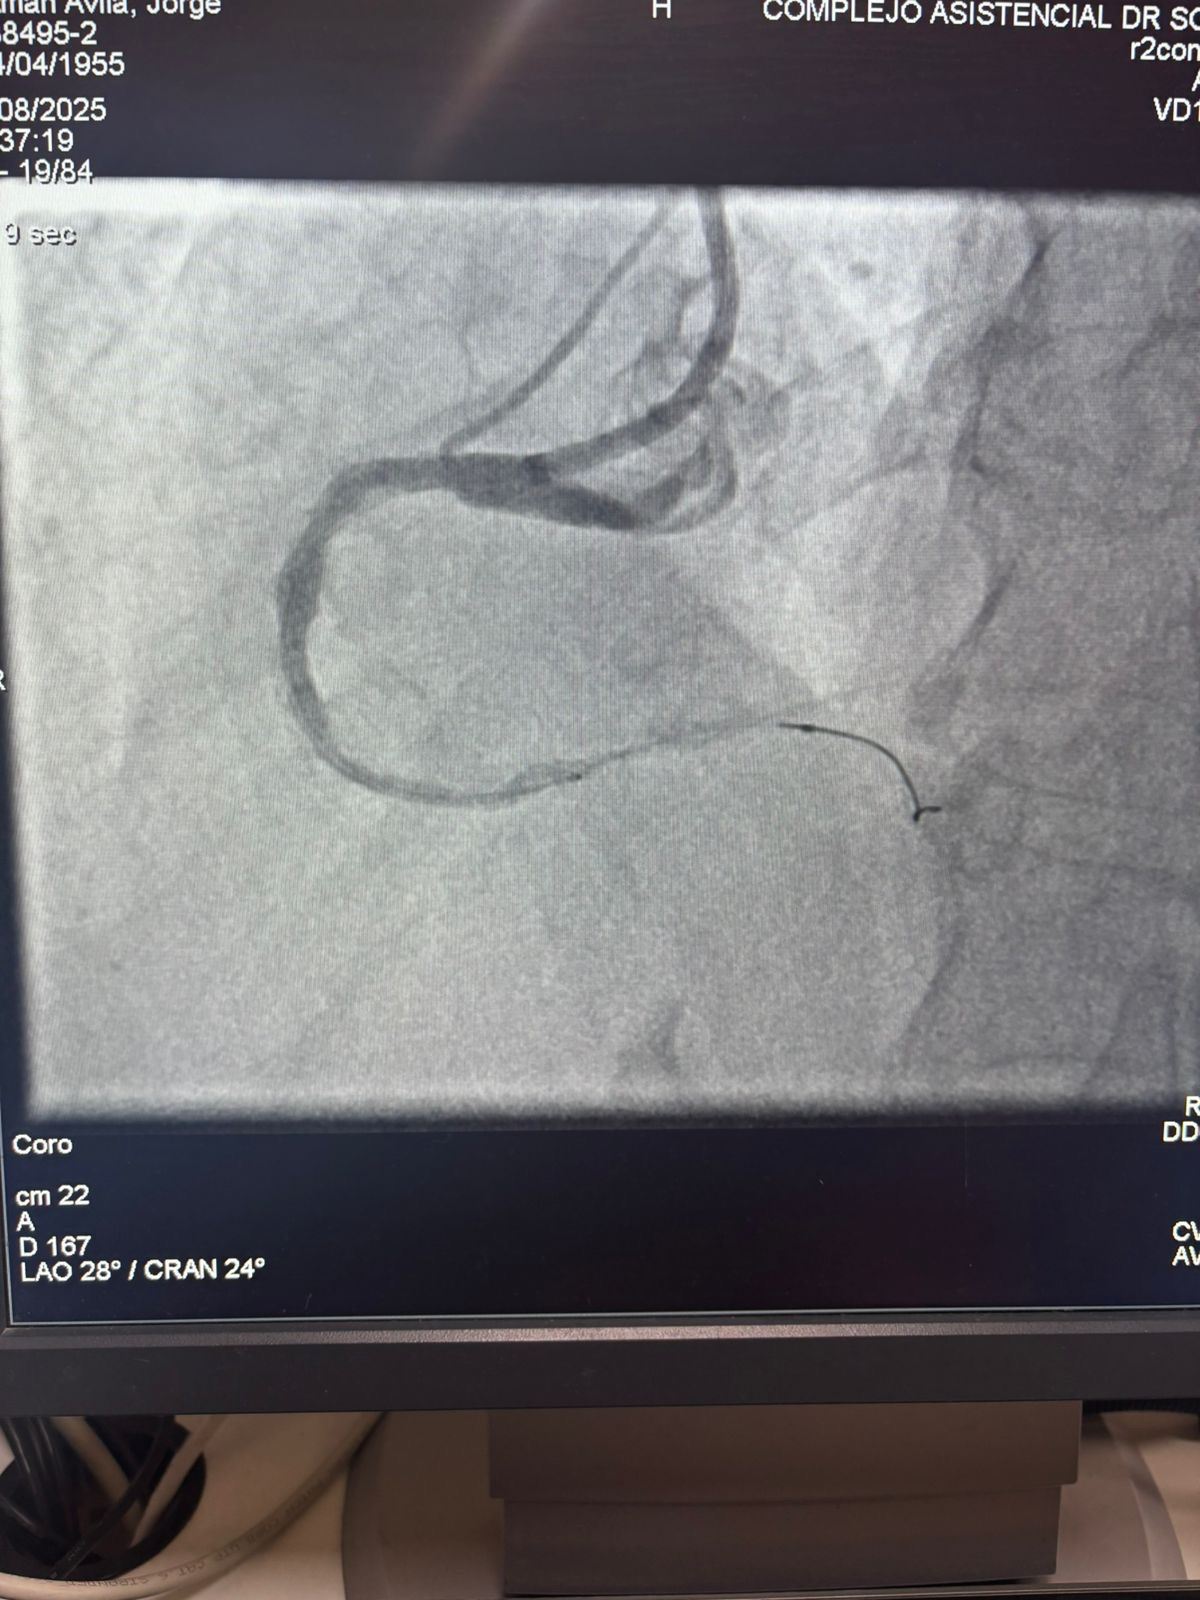

Wir sind stolz darauf, einen bemerkens werten Fall aus dem Krankenhaus Sótero del Río, Chile, zu teilen, in dem Dr. Martín Valde benito eine stark verkalckte Läsion in der rechten Koronar arterie (erste Kurve) mit unserem Vess crack Koronar-IVL-Ballon dilatation katheters ystem erfolgreich behandelte.

Das Verfahren erzielte hervorragende Ergebnisse, wobei die verkalckte Region effektiv geknackt und der Gefäß fluss wieder hergestellt wurde. Dies ist ein weiterer Meilenstein bei der Erweiterung des globalen Zugangs zu fortschritt lichen Lösungen für die komplexe Koronar verkalkung.

Der Vergleich zwischen den angio grafischen Bildern vor und nach dem Eingriff zeigt deutlich die signifikanten klinischen Auswirkungen unserer IVL-Technologie.